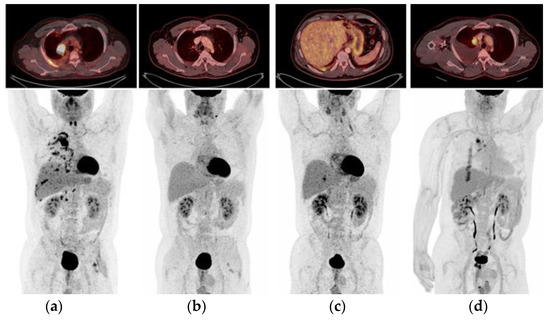

2.5. Case 5: Efficacy of Crizotinib-Osimertinib in EGFRm+ NSCLC Patient Acquiring High-Level MET Amplification after 26 Months of Treatment with Osimertinib

2.1. Case 1: Metastatic NSCLC with EGFR ex19del and Acquired MET Amplification: Short-Term Complete Response (CR) by Combining Crizotinib with Osimertinib